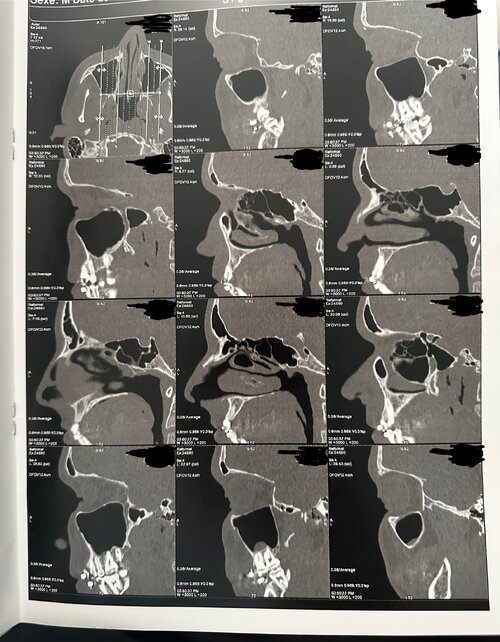

3. Airway and Oral Space

The sagittal (side) views reveal a moderately sized airway, with no extreme constriction but signs of limited space behind the soft palate and tongue. The soft palate extends close to the back wall of the throat (posterior pharynx), which may slightly narrow the oropharyngeal space. The tongue appears positioned relatively low, likely adapting to the narrow, high-arched palate, which offers limited lateral room for rest posture.

Together, these features suggest an airway that is functional but not maximally open, meaning airflow could be mildly restricted, particularly during sleep or nasal congestion.

3. Airway and Oral Space

The sagittal (side) views reveal a moderately sized airway, with no extreme constriction but signs of limited space behind the soft palate and tongue. The soft palate extends close to the back wall of the throat (posterior pharynx), which may slightly narrow the oropharyngeal space. The tongue appears positioned relatively low, likely adapting to the narrow, high-arched palate, which offers limited lateral room for rest posture.

Together, these features suggest an airway that is functional but not maximally open, meaning airflow could be mildly restricted, particularly during sleep or nasal congestion.